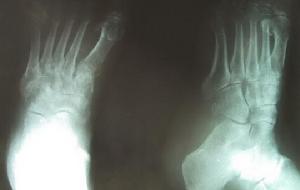

3、骨X线摄影:可发现骨萎缩像。